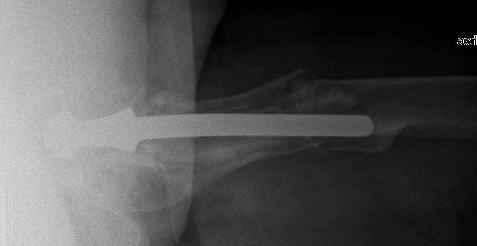

You transformed a cemented hip prosthesis to a cementless revision hip prosthesis with a little approach.

The nail tip is jammed. Since it is conical, it can only be jammed more with axial load.

I'd say yes because we use same 6 mm screws for femoral nailing and allow immediate weight-bearing regardless of fracture pattern.